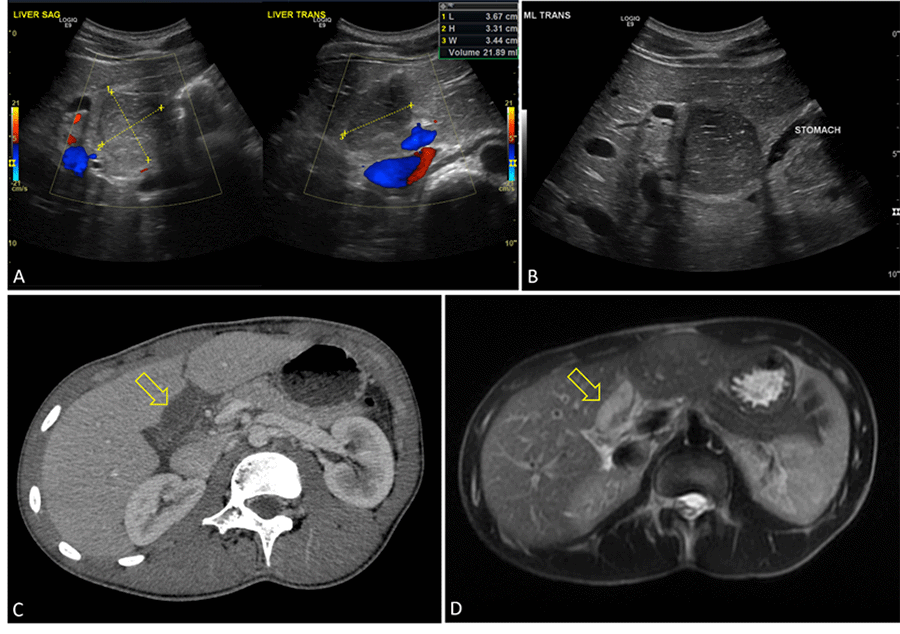

Laboratory evaluation revealed: white blood cell count 5.3 thou/mcL, hemoglobin 13.2 g/dL, creatinine 1.0 mg/dL, total bilirubin 1.4 mg/dL, alkaline phosphatase 159 unit/L, AST 32 units/L, ALT 39 units/L, and lipase 193 units/L. A right upper quadrant ultrasound was obtained and revealed a 36 × 33 × 34 mm cystic collection within the porta hepatis (Figure 1). The mass abutted the proximal duodenum, displaced the extrahepatic biliary ducts, and contained debris. The collection did not appear to communicate with the biliary system. An MRI was then obtained, which re-demonstrated the cystic mass. The contents were T1 hyperintense and appeared to have intraluminal debris. There was no communication to the biliary tree to suggest a choledochal cyst. The gall bladder was unremarkable. A HIDA scan was obtained and demonstrated prompt uptake in the gall bladder and normal flow into the duodenum. The ejection fraction was 47%. There was no evidence of communication with the cystic structure. After this work-up and improvement in symptoms, he was discharged home with a leading diagnosis of an inflamed duplication cyst.

Figure 1. Ultrasound Images and CT Scans. Published with Permission

A) Oval collection in porta hepatis isoechoic relative to liver parenchyma measuring 3.6 × 3.3 × 3.4 cm; B) Mass in subhepatic space, anterior to distal end of stomach; C) CT with cystic lesion and small amount of surrounding fluid; D) T2 MRI with cystic mass, slight mural thickening. No communication to biliary tree was found on magnetic resonance cholangiopancreatography.